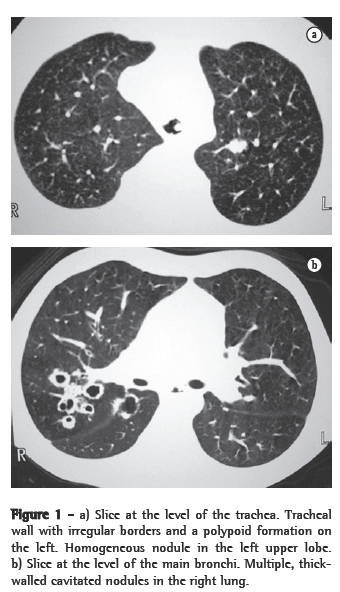

ResultsIn all eight cases, the CT scans revealed polypoid formations in the trachea. In one case, injury to one of the main bronchi was identified. Seven patients presented involvement of the pulmonary parenchyma. In all eight cases, there were cavitated polypoid lesions, with irregular internal borders and walls of various thicknesses, multilobulated in six cases and presenting confluence of the lesions in five (Figures 1 through 5). Solid nodules were seen in six patients. An air-fluid level was observed in only one patient. The lesions were predominantly in the lung bases in three patients and in the middle thirds in two, whereas they were evenly distributed in two. In one patient, the lesions were accompanied by a mass, and, in another patient, they were accompanied by consolidation. In the latter case (Figure 5), there was malignant degeneration in multiple lesions. Signs of air trapping were also observed in one case. There were no identified instances of lymph node enlargement or pleural effusion.

Chest X-rays are inferior to CT scans of the chest, especially those performed using spiral CT (volumetric acquisition), in the initial phases of pulmonary dissemination, due to the fact that CT better characterizes and allows better visualization of nodular tracheobronchial vegetation, Tomographic findings include focal or diffuse airway narrowing caused by the nodules. The nodules form on the mucosal surface, and their invasion into the lumen is best evaluated using CT.(3) These alterations are easily correlated with the disease when there is a clinical history of papillomatosis.(4) Other findings related to airway obstruction and accompanying infections are atelectasis, consolidations, air trapping and bronchiectasis.(2-4) In our sample, polypoid formations in the trachea were observed on all of the CT scans Seven patients presented involvement of the pulmonary parenchyma, characterized by cavitated polypoid lesions with irregular internal borders and walls of various thicknesses, with a multilobulated aspect and a tendency toward confluence. Solid nodules were seen in six patients. None of the patients presented lymph node enlargement or pleural effusion.